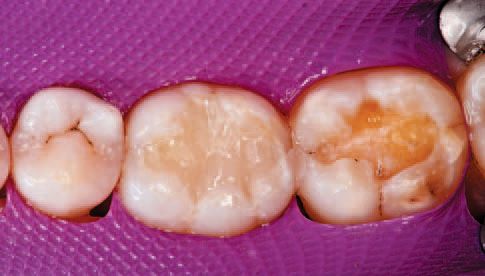

After inspecting the old amalgam restorations (Fig. 2), a rubber dam was then placed (Fig. 3). Next, using Sybron Dental’s Axis course diamond bur, KS3, the amalgam restorations and all damaged tooth structure were removed (Fig. 4).